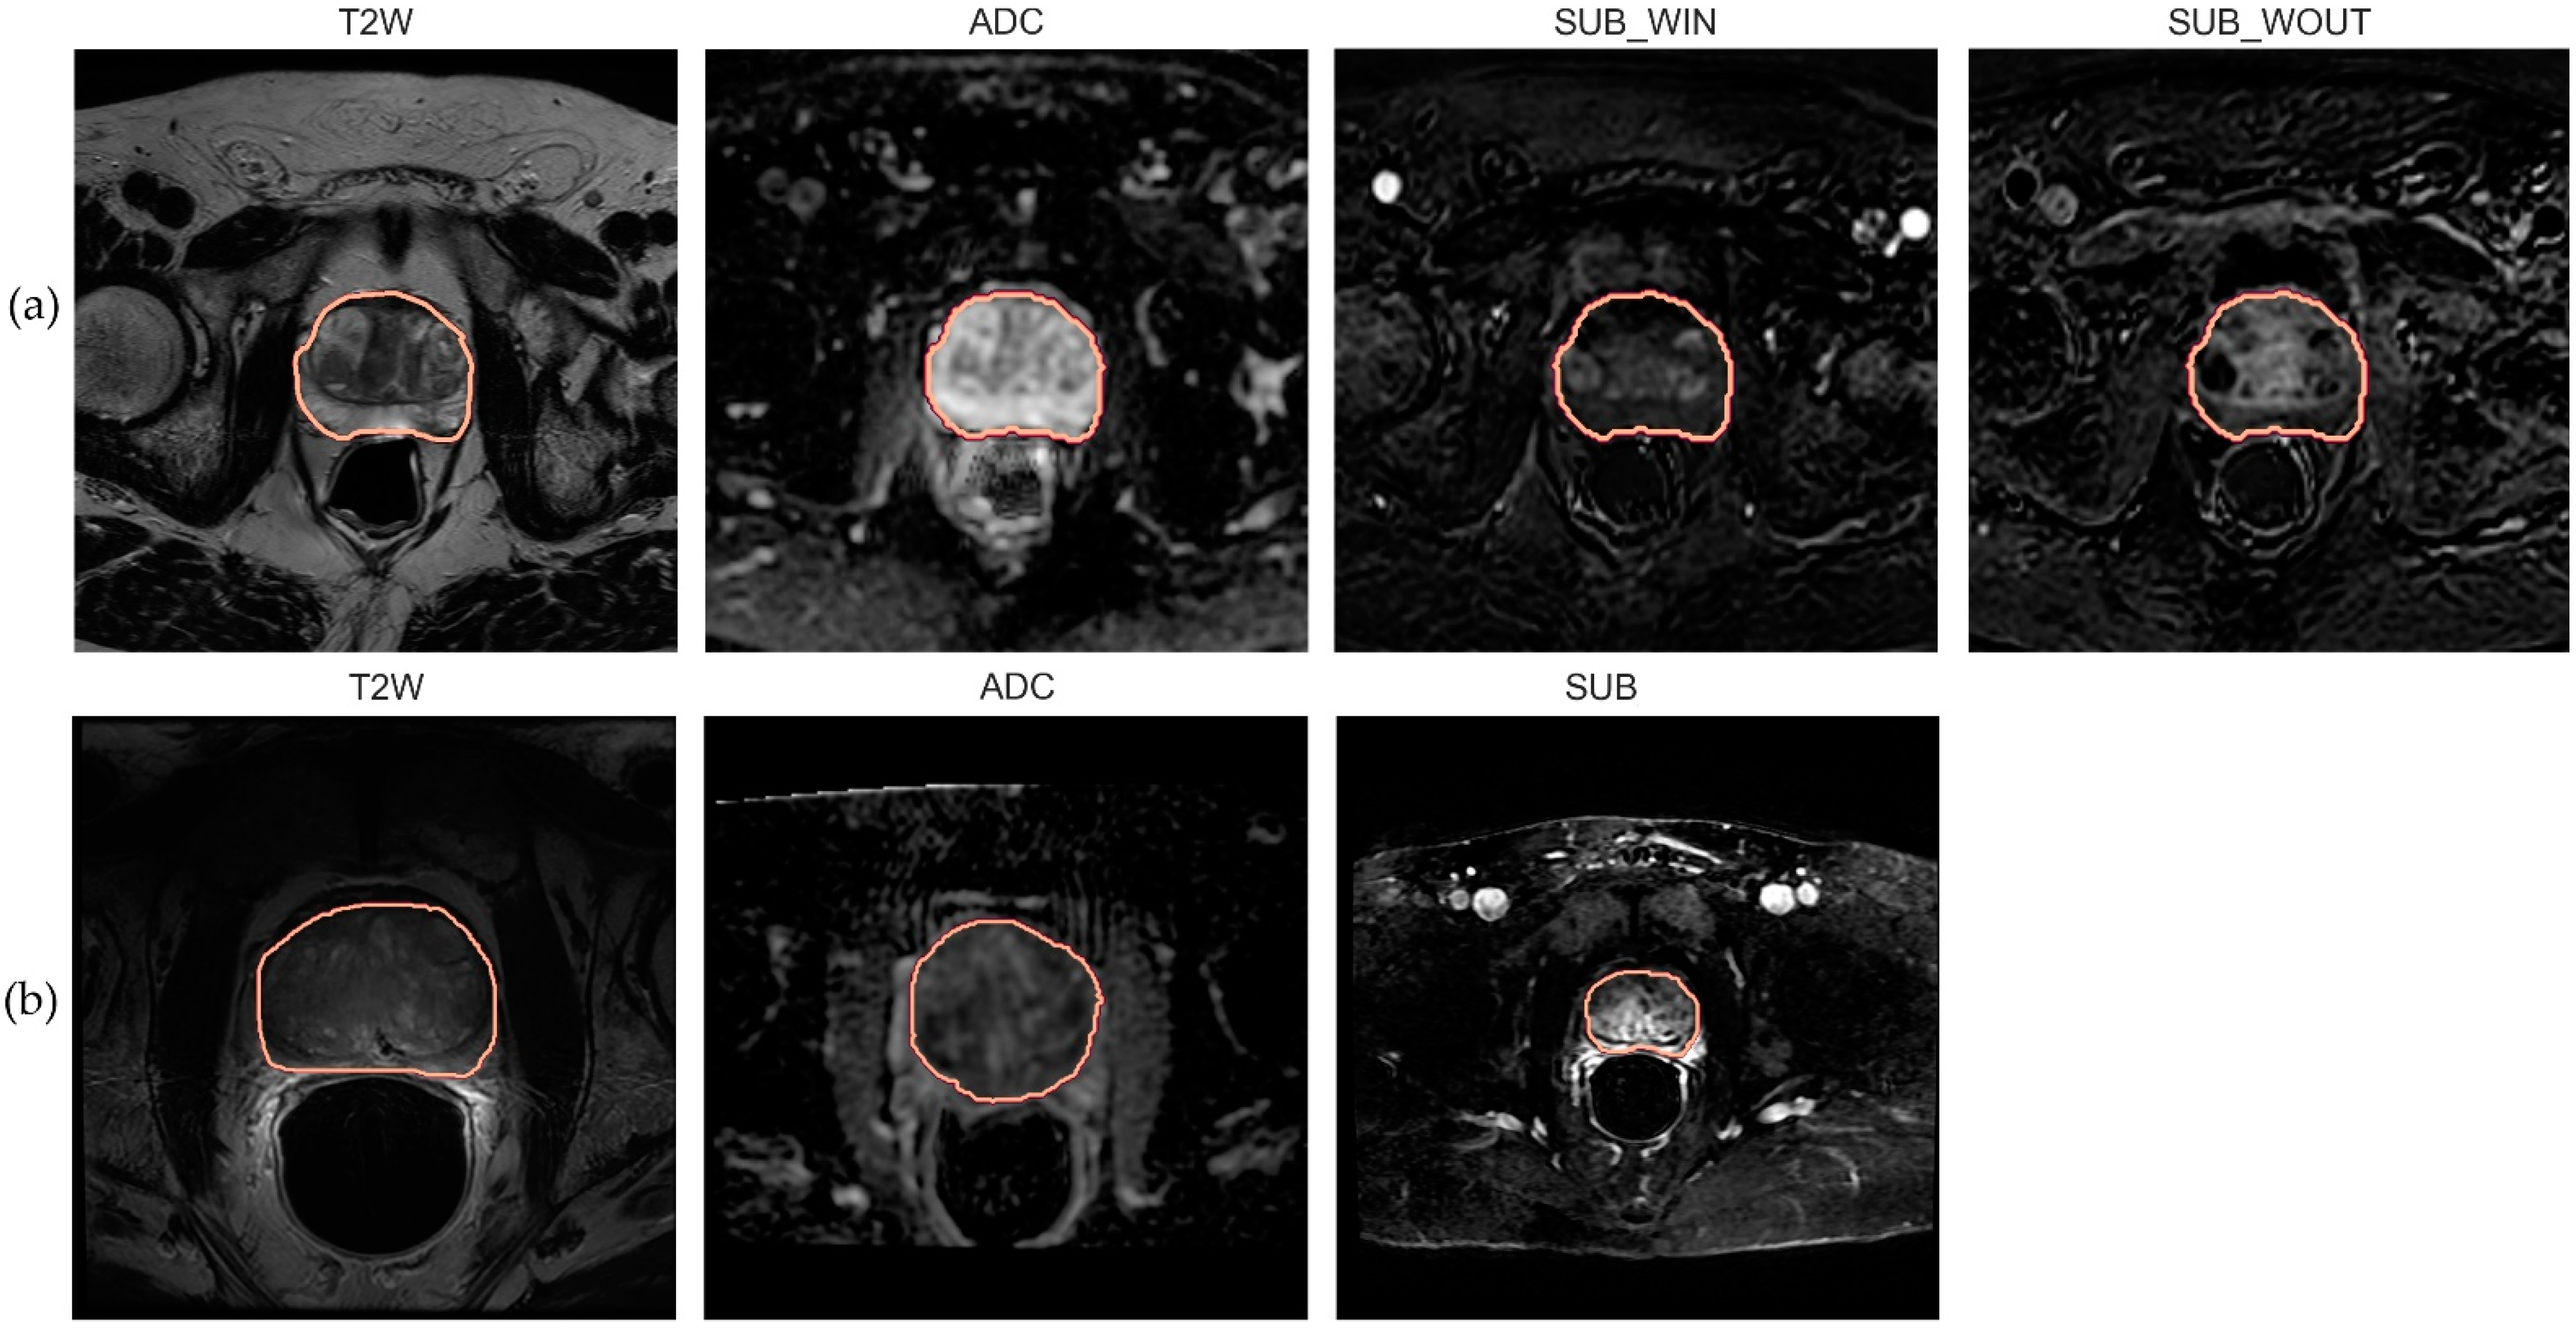

Figure 1.

Mid-level axial slice of the prostate gland with ROI annotation. (a) T2w, ADC, SUBwin, and SUBwout images associated with a random patient sampled from the internal population; (b) T2w, ADC, and SUB images associated with a random patient sampled from the external population.

We processed DWI and DCE sequences to generate the Apparent Diffusion Coefficient (ADC) and subtraction (SUB) maps. We derived the ADC map by computing the negative gradient associated with a least-square fit (straight line) over the DWI acquisitions with three b-values—0, 1500, and 2000 mm/s2. We processed the DCE acquisitions to generate two subtraction (SUB) maps describing the wash-in (SUBwin) and wash-out (SUBwout) phases of the contrast agent. The maps were computed by splitting the DCE acquisitions at a time point close to 90s in the temporal domain, i.e., SUBwin = DCE90+ε-DCE0 and SUBwout = DCEt_n-DCE90+ε. This was performed to capture the contrast agent inflow (wash-in) and outflow (wash-out) phases which are known to guide radiologists in assessing the malignancy in PCa management [42]. Here, t_n indicates the last DCE acquisition in the temporal domain. ε represents the deviation from the referenced time point. Table 1a presents a simplified summary of the internal dataset properties, and Figure 1, panel (a) highlights mid-gland level axial mpMRI slices of a sample patient from the population.

The in-built scanner software generated ADC and DCE SUB maps. The SUB map was computed as the difference between the phases involved in contrast bolus arrival to the baseline. Ultimately manual segmentation of the whole prostate gland (amongst other ROIs) was performed by an experienced radiologist for each sequence and was included in the dataset. Table 1b presents a simplified summary of the external dataset properties, and Figure 1, panel (b), highlights mid-gland level axial mpMRI slices of a sample patient from the population.